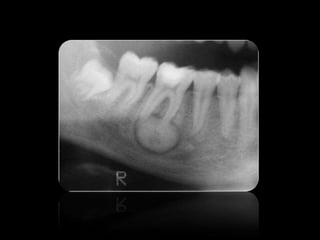

QUISTES

18.